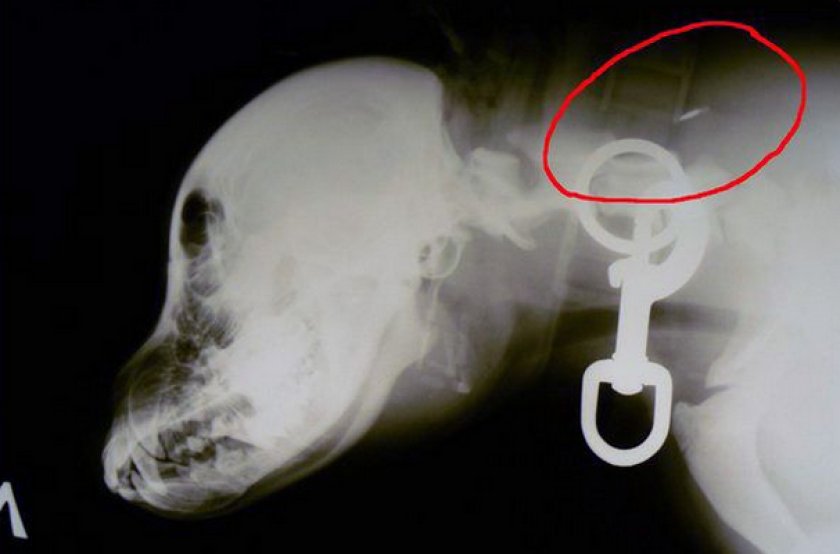

Микросхема, вживляемая кошке или собаке для идентификации, помещена в капсулу, которая весит чуть больше половины грамма. Ее размеры колеблются в пределах 1 см в длину и около 2 мм в ширину (для сравнения, примерно такую величину и вес имеют два рисовых зернышка, сложенные «цепочкой»).

Все очень просто и выглядит, как обычный укол. Так же быстро и не более болезненно. Капсула с микрочипом вводится кошке под кожу между лопатками при помощи специального аппликатора, который даже по внешнему виду похож на шприц. Он продается вместе с чипом и, разумеется, является одноразовым и стерильным.

Единожды введенная микросхема рассчитана на работу как минимум в течение четверти века, поэтому процедура всегда делается только один раз.

Место предстоящего укола обрабатывается спиртом, затем кожа на холке собирается в складку, игла аппликатора вводится под кожу полностью под 30-градусным углом, затем следует вдавить поршень шприца до упора, пока не послышится щелчок. Затем игла извлекается, и «мучения» окончены.

Владельцам чипированных кошек нужно также знать, что введенная между лопаток капсула может двигаться под кожей вашего питомца. Обычно траектория такой миграции не превышает пару сантиметров и не таит в себе никаких опасностей.

Считается, что холка — это идеальное место у кошки для вживления чипа именно потому, что здесь капсула лучше всего фиксируется и не будет «мигрировать», каким бы активным не был ее обладатель.

Но если место определено не очень удачно, а техника введения недостаточно выдержана, возможны ситуации, когда изначально введенная капсула не нашла «своего места» сразу.

Впрочем, нет никаких оснований считать, что такая ситуация является поводом для паники, она не влияет на работоспособность устройства (разве что процедура сканирования займет чуть больше времени, поскольку микросхему нужно будет отыскать под кожей) и самочувствие питомца, скорее всего, в течение какого-то времени микрочип в конце концов «установится».